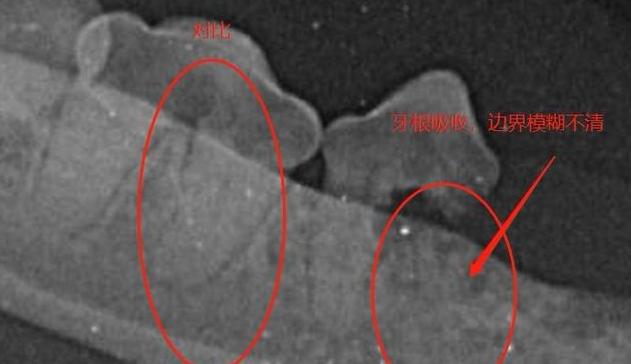

2.牙根吸收变短

有一些患者可能因为做过根管治疗之后,或者牙齿受过创伤进而导致牙根吸收的情况出现。